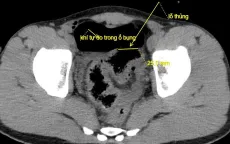

Bệnh nhân thủng đại tràng, tổn thương gan do sán lá gan

VTV.vn - Một tháng trước khi nhập viện, bệnh nhân T.B, 60 tuổi, trú tại Hà Tĩnh đau âm ỉ vùng thượng vị và hạ sườn phải, người mệt mỏi, chán ăn, sụt cân (5 - 6kg/tháng).